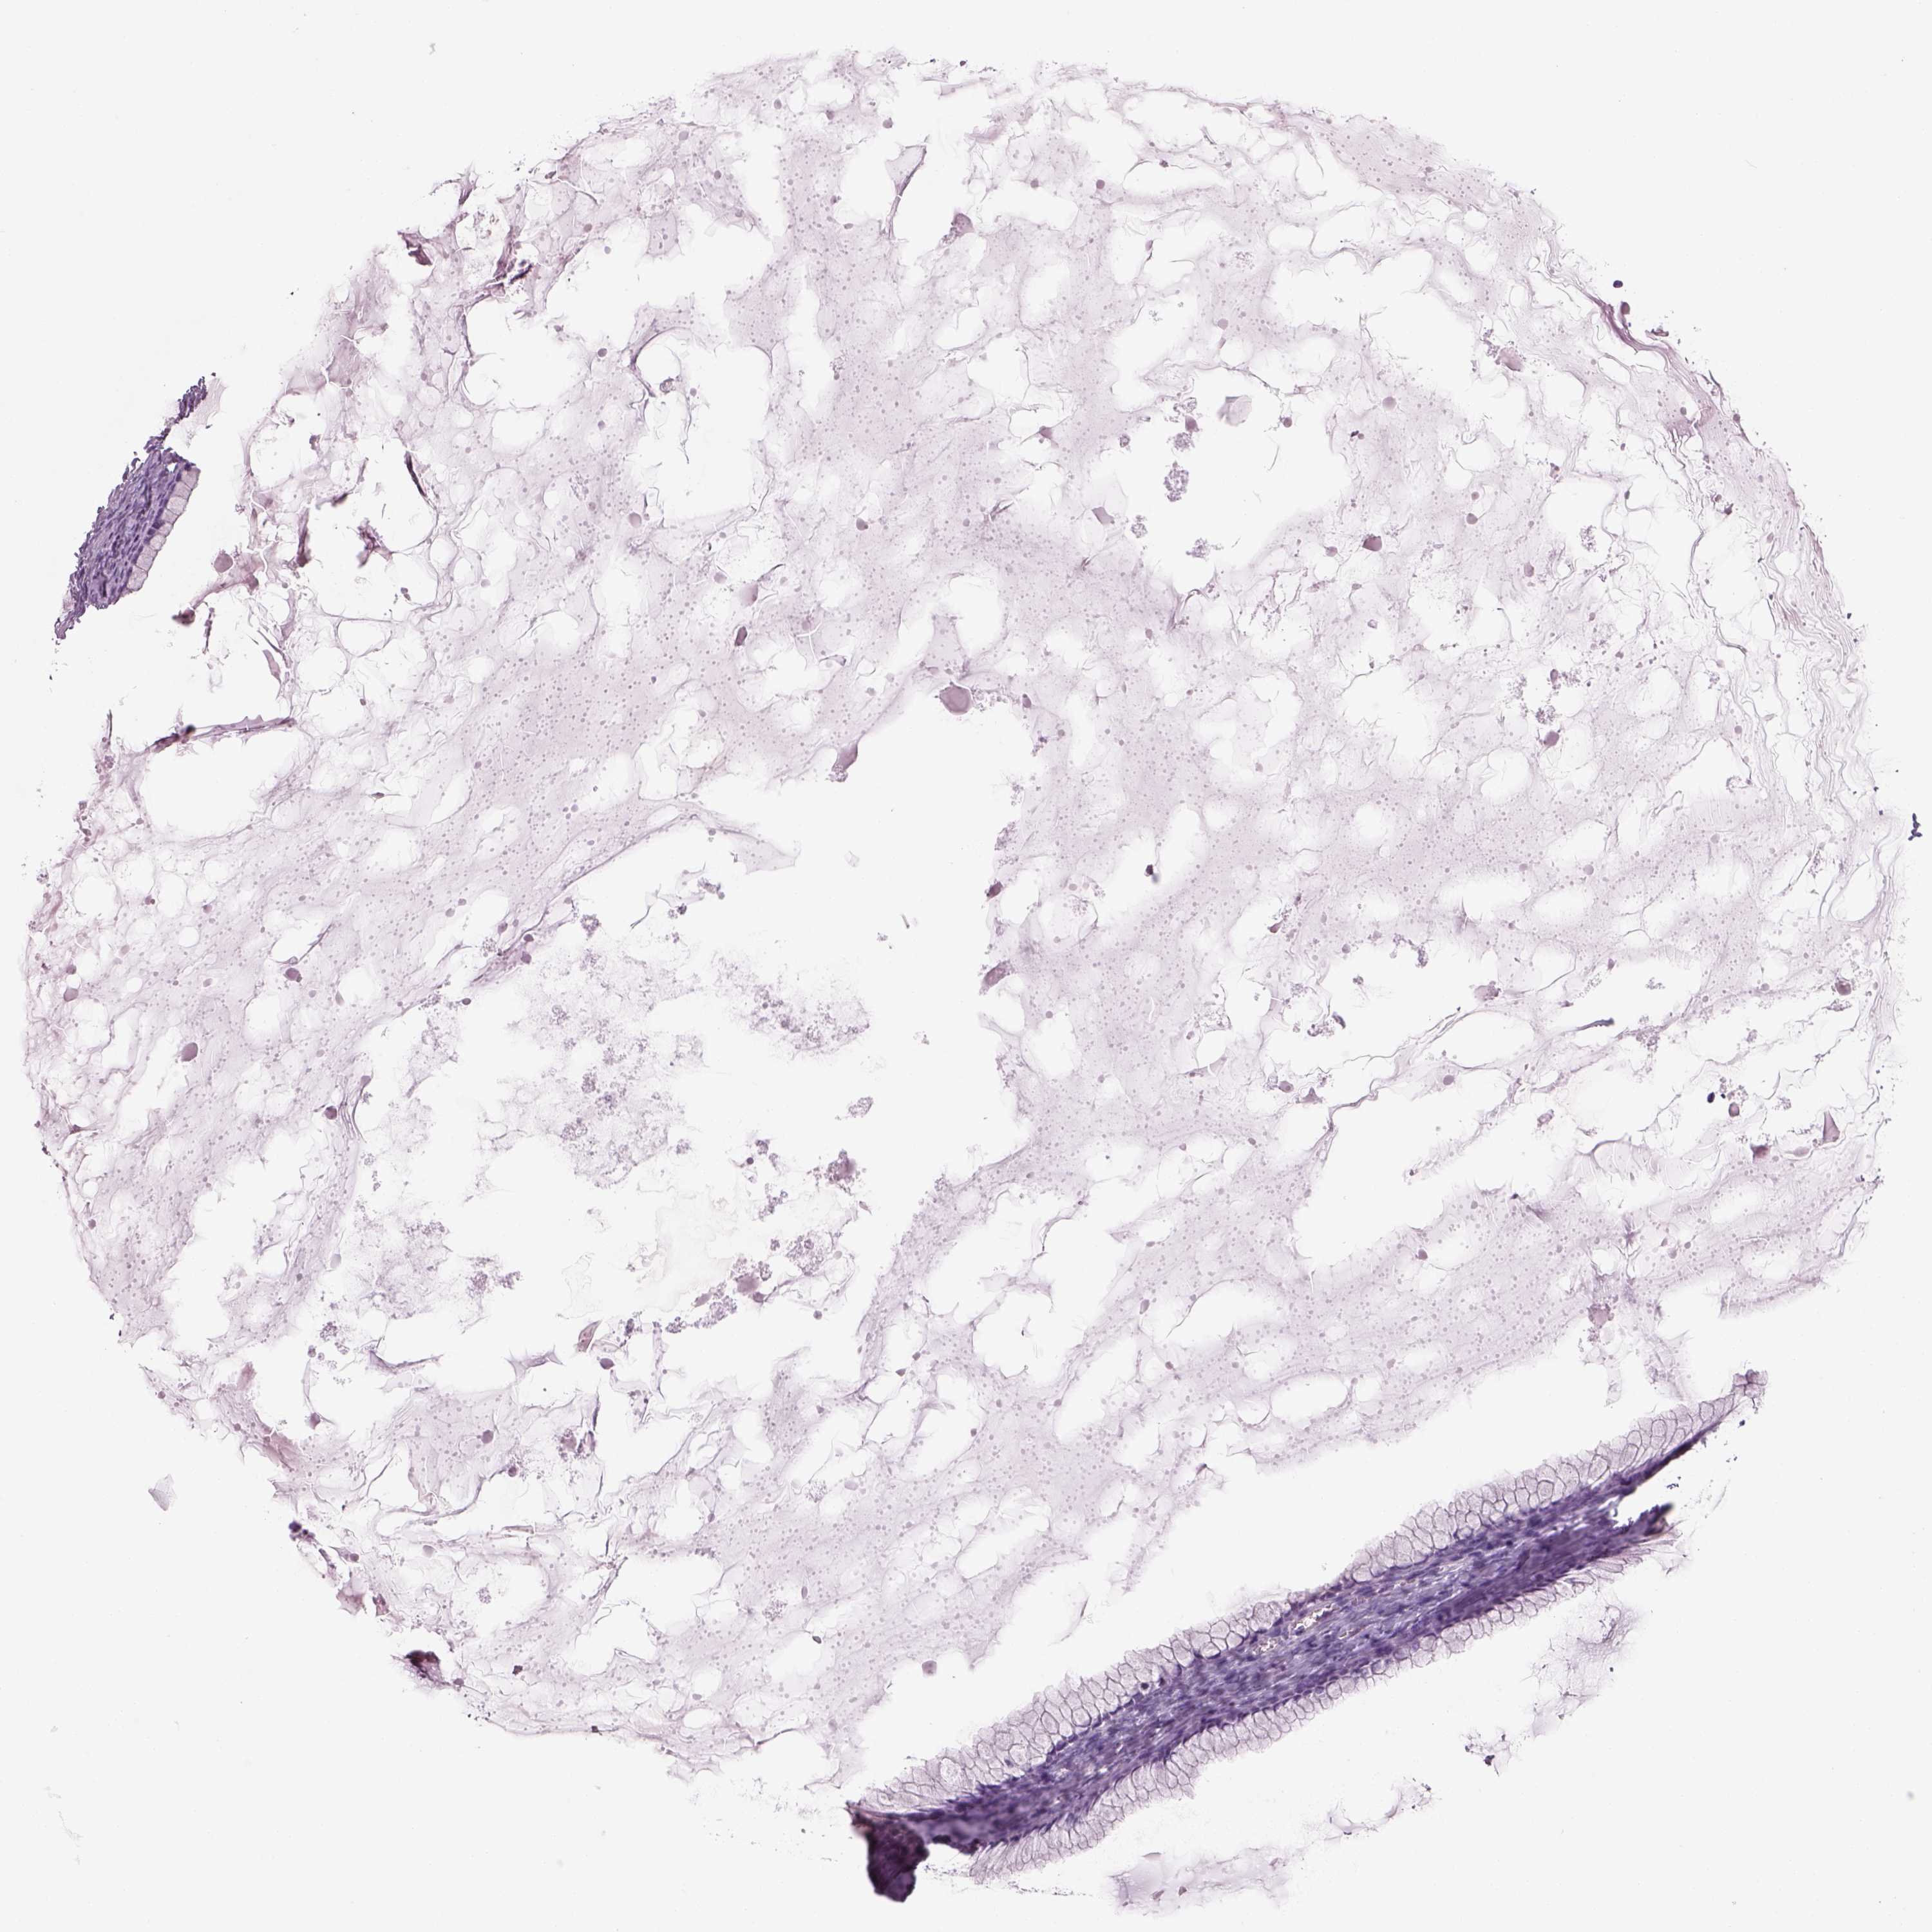

OVARIAN CANCER - Protein expressioni

A mouse-over function shows sample information and annotation data. Click on an image to view it in a full screen mode. Samples can be filtered based on level of antibody staining by selecting one or several of the following categories: high, medium, low and not detected. The assay and annotation is described here.

Note that samples used for immunohistochemistry by the Human Protein Atlas do not correspond to samples in the TCGA dataset.

Antibody stainingi

Antibody staining in the annotated cell types in the current human tissue is reported as not detected, low, medium, or high, based on conventional immunohistochemistry profiling in selected tissues. This score is based on the combination of the staining intensity and fraction of stained cells.

Each image is clickable and will lead to virtual microscopy that enables deeper exploration of all samples and also displays staining intensity scores, fraction scores and subcellular localization as well as patient and tissue information for each sample.

Antibody HPA073761

Cystadenocarcinoma, serous, NOS

Cystadenocarcinoma, mucinous, NOS

Carcinoma, endometroid